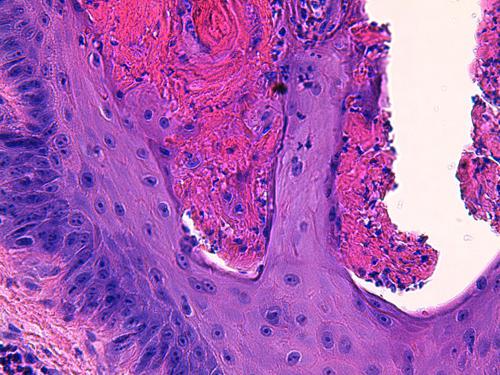

Photo 8 (Hémalun Eosine X 400) peau d’un coussinet : Vue rapprochée de la Photo 7 montrant

une zone de nécrolyse des cellules épidermiques, formant une zone grossièrement linéaire “creusant”

le massif épidermique et comblée d’hématies, de granulocytes, de débris cellulaires pycnotiques et d’un matériel fibrinoïde acidophile.

Légendes de la Photo 8 :

- Double flèche verte : zone de nécrolyse épidermique (grand axe perpendiculaire à la surface épidermique)

- Flèches jaunes : matériel hématique et fibrino-leucocytaire remplissant les zones de nécrolyse

- Étoiles vertes évidées : cellules inflammatoires lysées (granulocytes)

- Pointes de flèche turquoises : elles délimitent les zones nécrolytiques

- Étoiles blanches évidées : cellules épithéliales pycnotiques